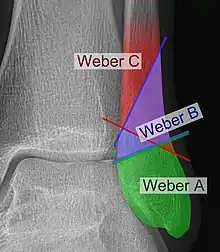

Danis–Weber classification on X-ray.

The Danis–Weber classification (often known just as the Weber classification) is a method of describing ankle fractures. It has three categories:[1]

Fracture of the fibula distal to the syndesmosis (the connection between the distal ends of the tibia and fibula). Typical features:

Fracture of the fibula at the level of the syndesmosis. Typical features:

Fracture of the fibula proximal to the syndesmosis. Typical features: